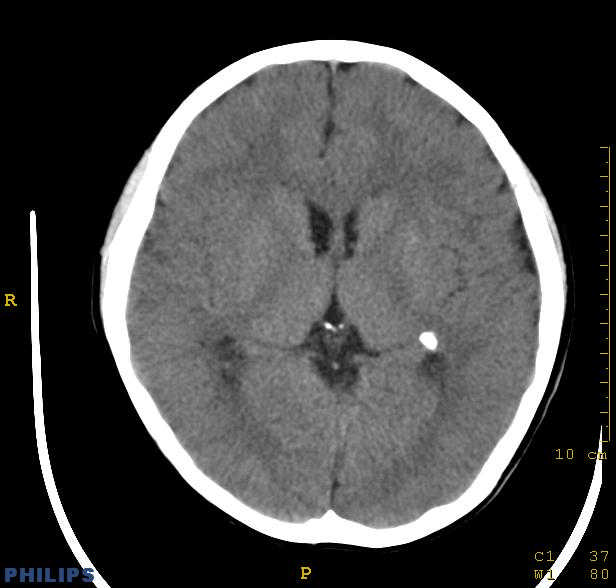

标题: PED0043:头颅平扫 男12岁.典型结节性硬化 [打印本页]

标题: PED0043:头颅平扫 男12岁.典型结节性硬化

典型结节性硬化

[病因病理]

结节硬化是常染色体显性遗传缺陷或基因突变引起的疾病,脑部病理可见神经胶质增生性硬化结节,位于大脑皮质、基底核及侧脑室壁的室管膜下。结节质地较硬,多有钙化。室管膜下结节可演变为巨细胞星形细胞瘤,亦可发生皮质错构瘤,常合并有其他器官畸形和肿瘤。

[影像学表现]

1.ct表现:

①室管膜下有多发性小结节状钙化影,也可为单发、不强化;小结节亦可未钙化;突入脑室可以强化;但有钙化者居多,颅内异常钙化高达90%。一般出生后2年即呈典型钙化。

②10%-15%的病例可能恶变为室管膜下巨细胞星形细胞瘤或其他胶质瘤。前者常位于室间孔附近,生长缓慢,增强扫描可产生异常强化。

③可见白质区脱髓鞘的低密度区。

④可伴脑灰质异位。

⑤脑室扩大系阻塞性脑积水或脑发育不良所致。